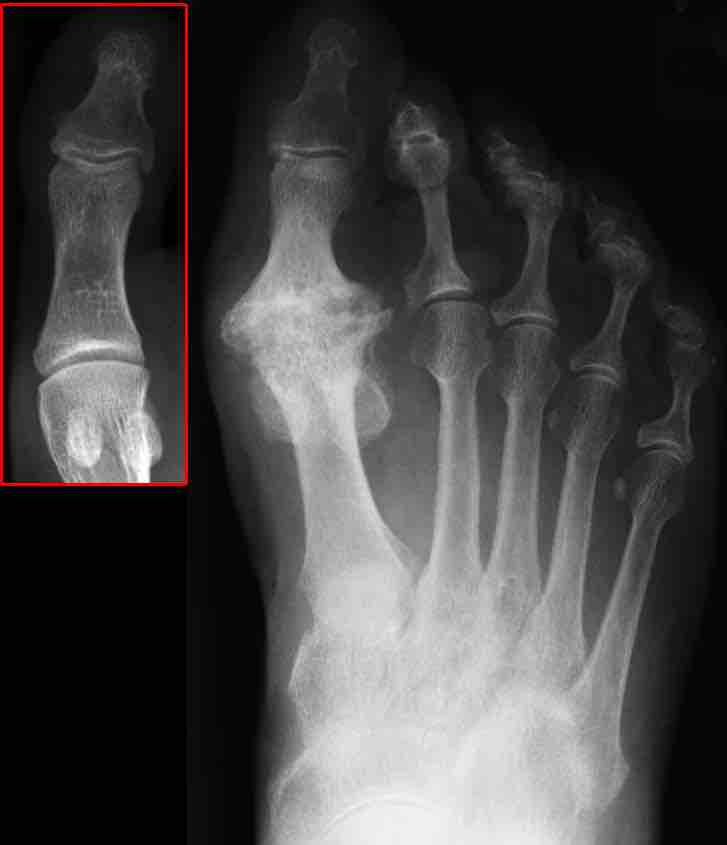

X-ray image of osteoarthritis of the big toe. The red box shows the normal joint.

Osteoarthritis